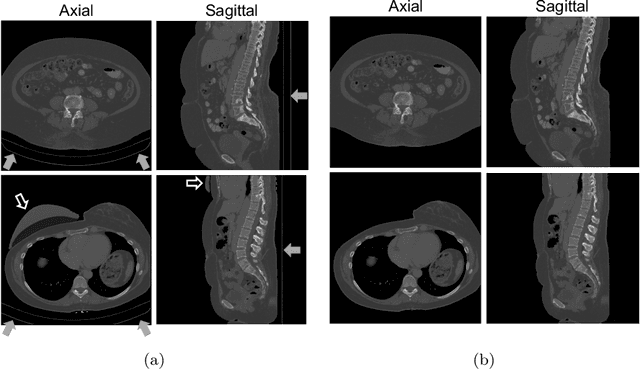

This study investigates the use of the unsupervised deep learning framework VoxelMorph for deformable registration of longitudinal abdominopelvic CT images acquired in patients with bone metastases from breast cancer. The CT images were refined prior to registration by automatically removing the CT table and all other extra-corporeal components. To improve the learning capabilities of VoxelMorph when only a limited amount of training data is available, a novel incremental training strategy is proposed based on simulated deformations of consecutive CT images. In a 4-fold cross-validation scheme, the incremental training strategy achieved significantly better registration performance compared to training on a single volume. Although our deformable image registration method did not outperform iterative registration using NiftyReg (considered as a benchmark) in terms of registration quality, the registrations were approximately 300 times faster. This study showed the feasibility of deep learning based deformable registration of longitudinal abdominopelvic CT images via a novel incremental training strategy based on simulated deformations.